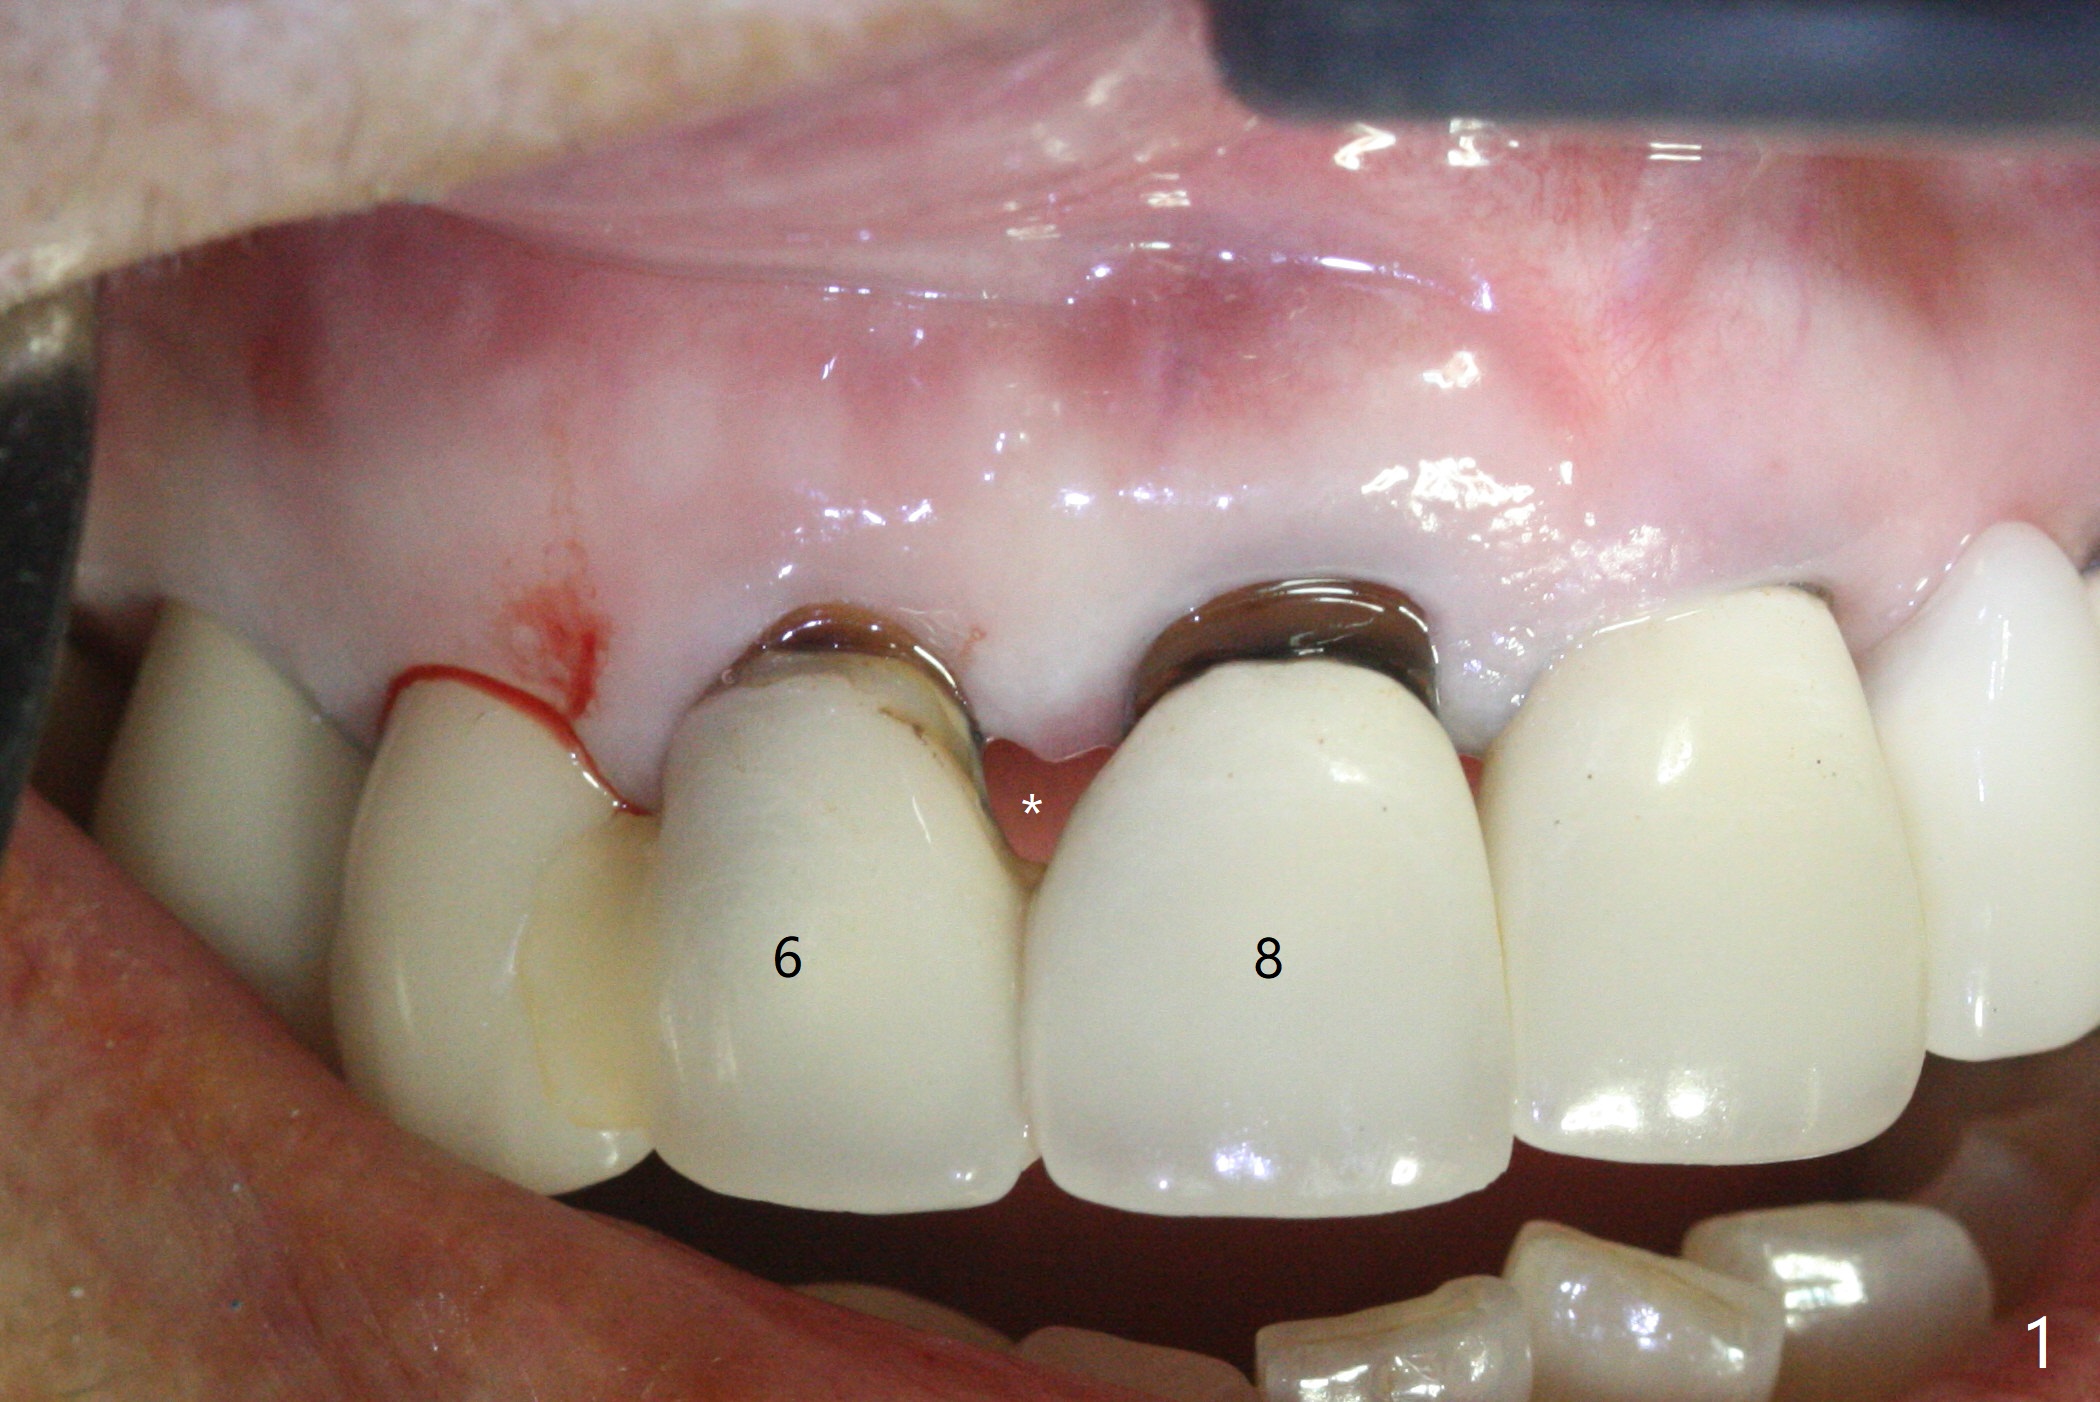

To reduce the large black triangle between the lateral incisor/canine and central incisor (Fig.1 *), osteotomy is not established mesial enough initially (Fig.2). Since the bone density is not high, trajectory change is not attempted. The ridge is wider within the socket. A relatively large 2-piece implant (3.5x13 mm) is placed (Fig.3), but a 4x5.7(2) mm abutment is incompletely seated (<). Use of 4.6 and 5.6 mm bone profile drills does not appear to solve the problem. The implant is backed up to the supra-gingival level so that it seems easier physically to insert the same abutment into the implant. Then both of them are torqued into the place together (Fig.4). An immediate provisional is fabricated to close the gingival embrasure as much as possible (Fig.5). Consider reducing the provisional margin (arrow) as early as possible postop. In fact the patient agrees to have a new crown made for #8 to further close the embrasure. The bone graft remains in place 4 months postop (Fig.6). The gingiva is healthy around the provisional 4.5 months postop (Fig.7). The gingival embrasure with a permanent restoration is smaller than that before treatment (Fig.8). Return to No Deviation Prevent Screw Loosening Prosthetic Planning Kit Webinars Xin Wei, DDS, PhD, MS 1st edition 02/11/2020, last revision 07/09/2020